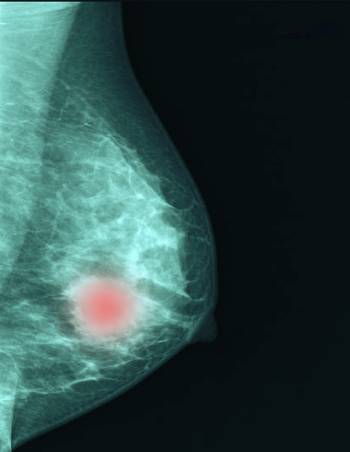

우리나라 유방암 진단 환자의 중간 나이가 꾸준히 높아지고 있지만, 40대 이하 젊은 층의 발생률도 증가세를 유지하고 있어 고령 중심의 서구와는 확연히 다른 발병 패턴을 보이는 것으로 분석됐다. 이른 초경과 늦은 폐경, 저출산 등의 영향으로 앞으로 유방암 발병률은 한동안 더 오를 가능성이 크다고 학계는 전망한다.

한국유방암학회는 지난해 제주도 그랜드조선 제주에서 열린 추계학술대회에서 '한국인 유방암의 현주소'를 발표했다. 학회가 국가 암 등록사업자료를 분석한 결과, 유방암은 앞으로도 한국인 여성에서 가장 많이 발생할 암종으로 집계됐다. 연평균 4.6%씩 발생률이 증가해 2021년 기준 연령표준화 발생률은 연간 10만명당 68.6명을 기록했고 이대로라면 3만명 이상의 신규 환자가 발생하는 것은 시간문제라는 게 학회의 설명이다. 국내 여성 암 발생의 5분의 1에 해당하는 수치다.

연령대별 유방암 발생률을 보면 2021년 기준 40대 유방암 환자 수는 8589명으로 전 연령대를 통틀어 가장 많았다. 다음으로 △50대 8447명 △60대 5978명 △70대 2611명 △30대 2096명 순이다. 유방암 진단 중간 나이는 2000년 46.9세에서 2010년 이후 50세를 넘어선 뒤 지속해서 높아져 2021년 53.4세를 기록했다. 인구 고령화 추세 속 폐경 후 유방암 환자 수가 늘고 있음을 시사하는 결과다.

다만, 미국처럼 연령이 높아질수록 유방암 발생이 증가하는 '서구화 패턴'으로의 변화일지는 좀 더 지켜봐야 한다는 게 학회의 판단이다. 박세호 세브란스병원 유방외과 교수는 "이번 분석 결과 한국 여성의 유방암 발생률은 50대 초반까지 증가세를 보이다 그 이후로는 점차 감소하는 특징을 보였다"며 "서구와는 다른 양상으로 향후 발생 양상을 좀 더 주시할 필요가 있다"고 밝혔다.

학회는 유방암 진단 나이가 점차 높아지고 있는 상황에서도 '젊은 유방암'이 줄지 않는 이유로 서구화된 식생활과 음주·흡연 등 생활 습관의 변화, 운동 부족, 비만, 유전력 등을 꼽았다. 여기에 늦은 결혼이나 비혼 여성의 증가, 출산율의 저하와 수유 감소, 이른 초경과 늦은 폐경에 따른 에스트로겐 노출 기간의 증가에 따른 치밀 유방 여성 증가 등이 더해지면서 폐경 이후 유방암 진단도 늘어나고 있다고 분석한다.

한원식 한국유방암학회 이사장(서울대병원 유방외과 교수)은 "국내 유방암 발생 건수가 가파르게 증가하지만 미국 등 서구 선진국의 발생률과 비교하면 아직 70~80% 정도"라며 "이를 감안하면 향후 10년 이상 증가세를 유지할 것으로 보인다. 유방암 검진 등의 대국민 홍보를 강화하고 한국인만의 유방암 예방과 조기 검진, 진단 및 치료 등을 아우르는 맞춤 프로그램을 마련해야 한다"고 말했다.